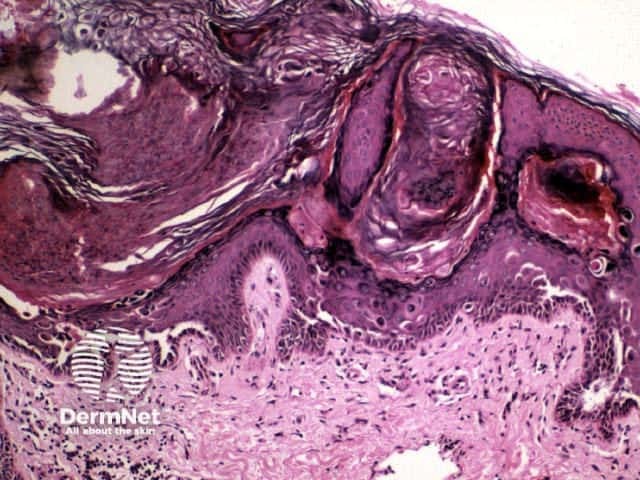

Darier histology has the following features:

Low power view

Close-up